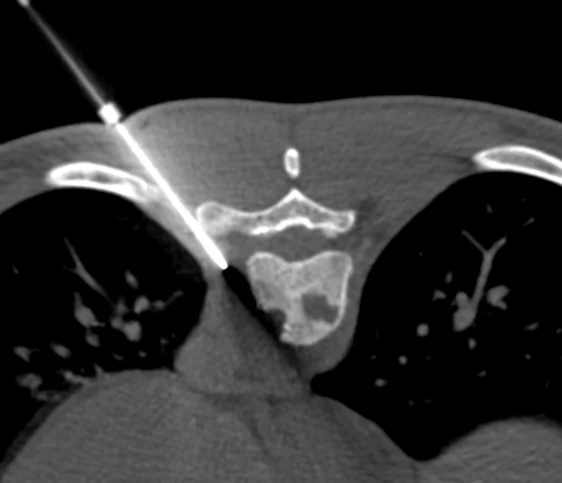

Various image guided procedures are performed in department for diagnostic as well as therapeutic purpose.

Diagnostic procedures : Image guided biopsy and needle aspirations are accurate and safe since it is performed under image guidance.

CT guided procedures : Problem associated with backache like degenerative changes in sacroiliac joints, facet joints, pain in the tail bone regions are treated by CT guided selective joint and nerve root injections. Complex and difficult to access areas in body can be approached by CT scan guidance for biopsy and drainage procedures.